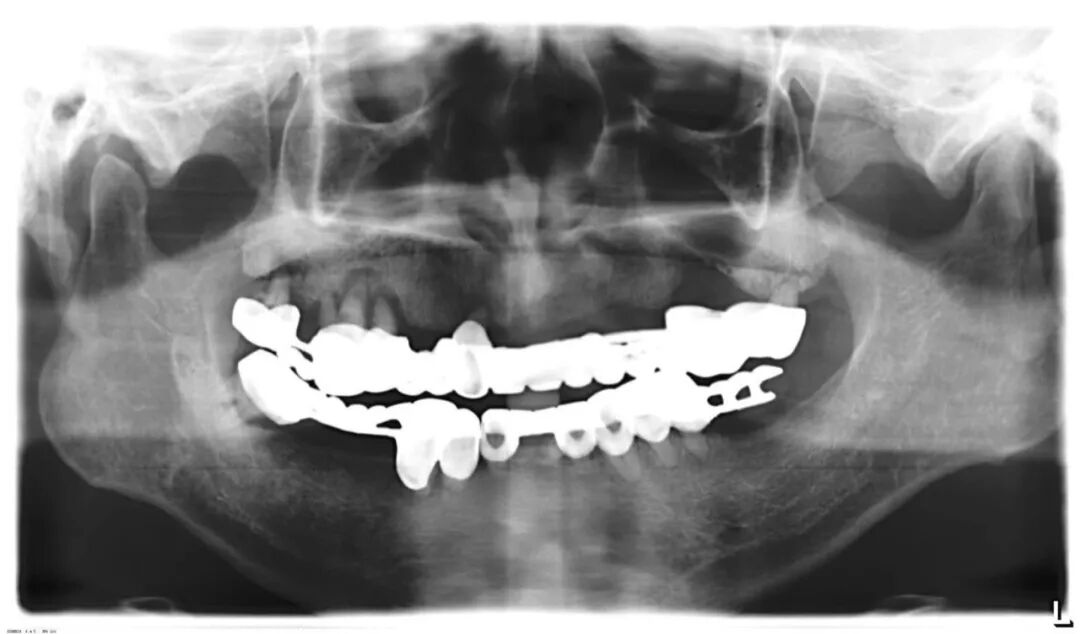

另外,烤瓷桥中的极品——“长江大桥”现象,则是普遍存在于中国各城市各基层牙科的不规范现象,与普通烤瓷桥不同,其本质是一种违反口腔生物力学原理的设计,其最常见的转归是全口牙报废,临床上很多先在基层做,两三年后去医院拆,对口腔健康的影响令人咂舌。

这样的病例实在太多,公立医院和部分高端民营口腔机构每年都要拆除很多例,后续治疗则费时费事费钱费脑筋,而且此类患者来源于社会各阶层,我见过的病例包括一些同事医生(非牙医)的父母,医生的健康意识不代表其家人,而你无法想象其中一例是拥有几百亿资产的企业家,医疗信息不对称应该是主要因素。